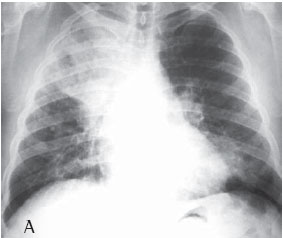

Quanto à classificação radiológica das grandes opacidades na radiografia de tórax verificou-se que: 23 pacientes apresentaram grande opacidade do tipo A (30,7%), 25 do tipo B (33,3%) e 27 do tipo C (36%) (Figuras 1A e 1B). Dos casos analisados, 74 apresentaram massas conglomeradas bilaterais, e apenas 1 apresentou lesão unilateral (Figuras 2A e 2B).

Mais da metade dos pacientes com silicose complicada apresentou na radiografia de tórax grandes opacidades dos tipos B e C, o que denota a gravidade da doença nestes pacientes.

De todos os casos analisados (n = 75), apenas um apresentou grande opacidade unilateral simulando massa tumoral, sendo o diagnóstico de silicose feito através de toracotomia com biópsia pulmonar a céu aberto. Lesões solitárias de FMP são freqüentemente confundidas com câncer de pulmão. Considerando-se a maior incidência de câncer de pulmão nesses pacientes, é importante fazer uma abordagem diagnóstica para efetivamente diferenciar as lesões malignas das lesões benignas pneumoconióticas.(19)